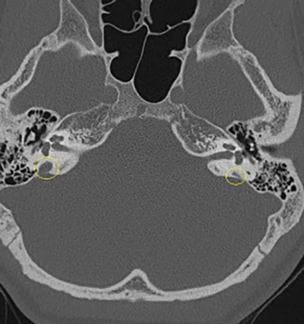

The Enigma of Enlarged Vestibular Aqueduct Syndrome

Patients may hold the key to improving EVA diagnosis and outcomes Innovations in Otolaryngology - Head & Neck Surgery - Summer 2018 Todd Otteson, MDThanks to a special internet website portal and database developed at University Hospitals...

Demystifying Enlarged Vestibular Aqueduct Syndrome

New national EVA patient registry will clarify prognosis, identify risk factors for EVA-related hearing loss Innovations in Pediatrics - Summer 2016 - View Full PDF Todd Otteson, MD, PhD It’s a clinical conundrum: An enlarged vestibular...